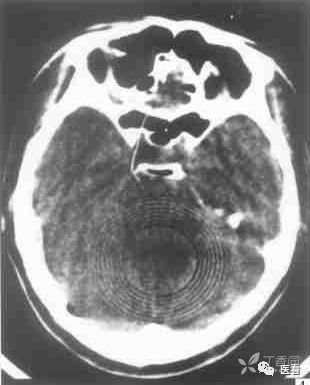

9 设备因素产生的同心圆伪影

此类伪影大多可以采用水模校准后消除